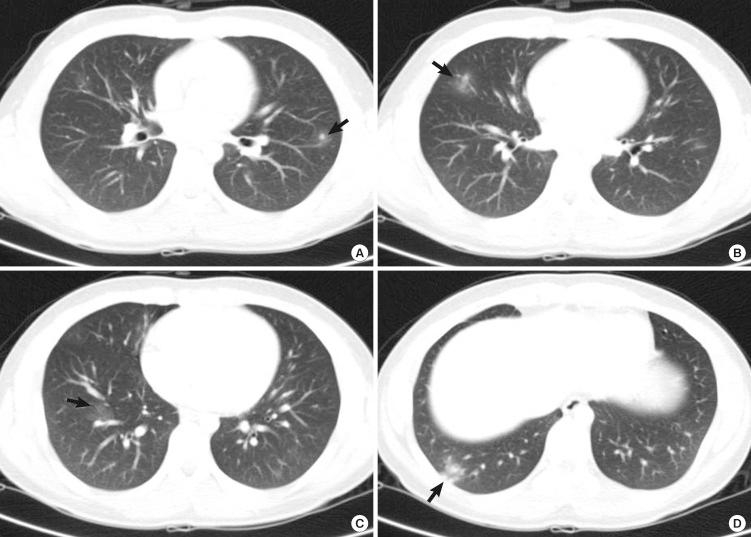

Recently reports on toxocariasis are increasing by serodiagnosis in Korea. A previously healthy 17-yr-old boy complained of headache, fever, dyspnea, and anorexia. He showed symptoms and signs of eosinophilic meningitis with involvement of the lungs and liver. Specific IgG antibody to Toxocara canis larval antigen was positive in serum and cerebrospinal fluid by ELISA. He took raw ostrich liver with his parents 4 weeks before the symptom onset. His parents were seropositive for T. canis antigen but had no symptoms or signs suggesting toxocariasis. This is the first report of toxocariasis in a family due to ingestion of raw ostrich liver in Korea.

近来,通过血清学诊断,韩国的旋毛虫病报告病例有所增加。一名此前健康的 17 岁男孩主诉头痛、发热、呼吸困难和食欲不振。他出现了嗜酸性粒细胞性脑膜炎的症状和体征,并累及肺部和肝脏。酶联免疫吸附试验(ELISA)显示,血清和脑脊液中针对犬蛔虫幼虫抗原的特异性 IgG 抗体呈阳性。他在症状出现前 4 周与父母一起食用了生鸵鸟肝。他的父母对 T. canis 抗原呈血清学阳性,但没有出现提示旋毛虫病的症状或体征。这是在韩国因食用生鸵鸟肝导致家庭感染旋毛虫病的首例报告。